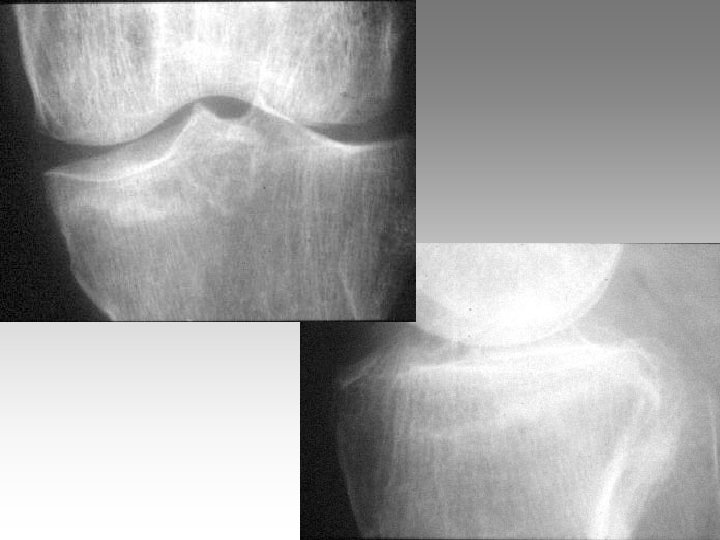

Face debout Schuss Face debout extension Intérêt du cliché de face en position Schuss